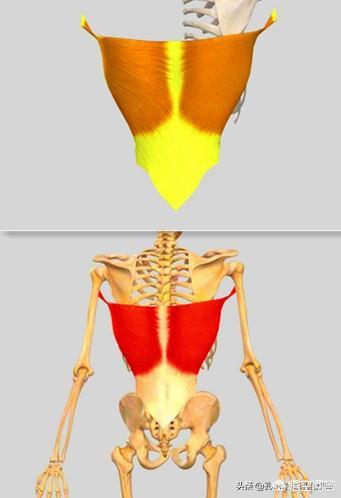

Comme indiqué ci-dessus, ce muscle est anatomiquement ce que l'on appelle un "levator scapulae (anatomie)". Il se développe d'une part sur l'apophyse transverse des vertèbres cervicales 1 à 4, et d'autre part à l'endroit même où se trouve le point douloureux (l'angle supérieur interne de l'omoplate). Sa fonction principale est la suivante :Lorsque la fin du point de douleur est fixéeLa tête et le cou sont inclinés vers l'arrière lorsque les deux côtés sont contractés et raccourcis.Lorsque la tête est baissée pendant une longue période, elle s'étire progressivement lorsque la tête est tirée vers l'avant, jusqu'à ce qu'à la limite, lorsqu'il n'est plus possible de l'étirer davantage, il y ait une douleur à l'angle supérieur interne de l'omoplate, à l'extrémité stationnaire.。

2) Deuxième raison : bien que rares, lesFacilement mal diagnostiquéC'est le problème des releveurs de l'omoplate décrit plus haut. Une autre structure importante est le muscle oblique postérieur, comme indiqué ci-dessous :

Ce muscle, l'oblique postérieur, se développe à une extrémité sur les vertèbres cervicales 6 et 7 et sur l'apophyse transverse.L'autre extrémité se trouve sur la deuxième nervure du côté arrière.(b) Si elle est due au fait qu'elle est souventEn baissant la tête, ce muscle se raccourcit et se tend, ce qui provoque une douleur au niveau de la cage thoracique.. Ici, bien qu'elle ne soit pas attachée à l'omoplate, dans une large mesure, la douleur dans cette position n'est pas un très petit point de douleur confiné, le point de douleur de l'omoplate.Il s'agit souvent d'un domaine qui fait l'objet d'un diagnostic erroné.La figure ci-dessous présente les éléments suivants :

Avec une telle zone de douleur, il est probable qu'il s'agisse d'un problème au niveau du muscle oblique postérieur, facilement confondu avec un problème au niveau du muscle releveur de l'omoplate.La douleur provoquée par le muscle oblique postérieur est plus profonde et plus supérieure.。

La première raison est quePiégeage du nerf scapulaire dorsalRésultat. Le nerf scapulaire dorsal innerve principalement les muscles scapulaire et rhomboïde juste après la naissance.La région du bord médial de l'omoplate est située à l'endroit où s'attache le muscle rhomboïde, comme le montre l'illustration ci-dessous :

Un tel physique affectera directement le fascia rhomboïde attaché à l'omoplate dans le dos, vous voyez où les rhomboïdes se développent ?

Comme indiqué ci-dessus, le muscle rhomboïde est composé de deux parties, le petit muscle rhomboïde en haut et le grand muscle rhomboïde en bas, qui partent tous deux de l'apophyse épineuse sur la ligne médiane de la colonne vertébrale jusqu'au bord médial de l'omoplate. C'est par l'aspect du physique décrit ci-dessus que leLes rhomboïdes sont ensuite étirés sur les côtés, comme si l'on tirait sur un sac en plastique, et à un certain moment, une douleur apparaît dans la zone du bord médial de l'omoplate.L'arrière des épaules et l'arrière du corps ressentent comme un poids lourd. En même temps, vous aurez une sensation d'enfoncement et de lourdeur à l'arrière des épaules, comme si vous portiez une lourde charge sur votre dos ; et bien sûr, les rhomboïdes sont souvent faibles parce qu'ils ont été étirés pendant longtemps.Une omoplate à aile externe dont le bord médial fait saillie vers l'extérieur.Les femmes prédominent.

La troisième raison est queProblèmes avec le latissimus dorsiqui est aussi souvent négligé cliniquement car il existe un autre faisceau de fibres reliant le muscle latissimus dorsi à l'angle du sous-scapulaire.

De nos jours, de nombreuses personnes qui sont sédentaires pendant de longues périodes ont des muscles fessiers étirés et faibles, et souffrent souvent de douleurs lombaires ou de douleurs dans la région de l'angle inférieur de l'omoplate, qui sont causées par des tensions dans le fascia thoraco-lombaire reliant les muscles latissimus dorsi et gluteus maximus.Le muscle latissimus dorsi compense la faiblesse du muscle grand fessier et produit une tension qui tire sur l'angle du sous-scapulaire.。